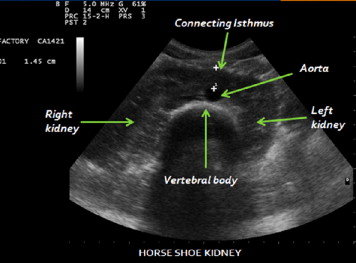

12. kép:

Patkóvese

Ezen a képen egy fejlődési variáció látható. Ez a patkóvese. A képen jól látható a jobb és a bal vese és az azokat összekötő parenchyma híd ami a gerinc és a hasi főverőér előtt helyezkedik el.